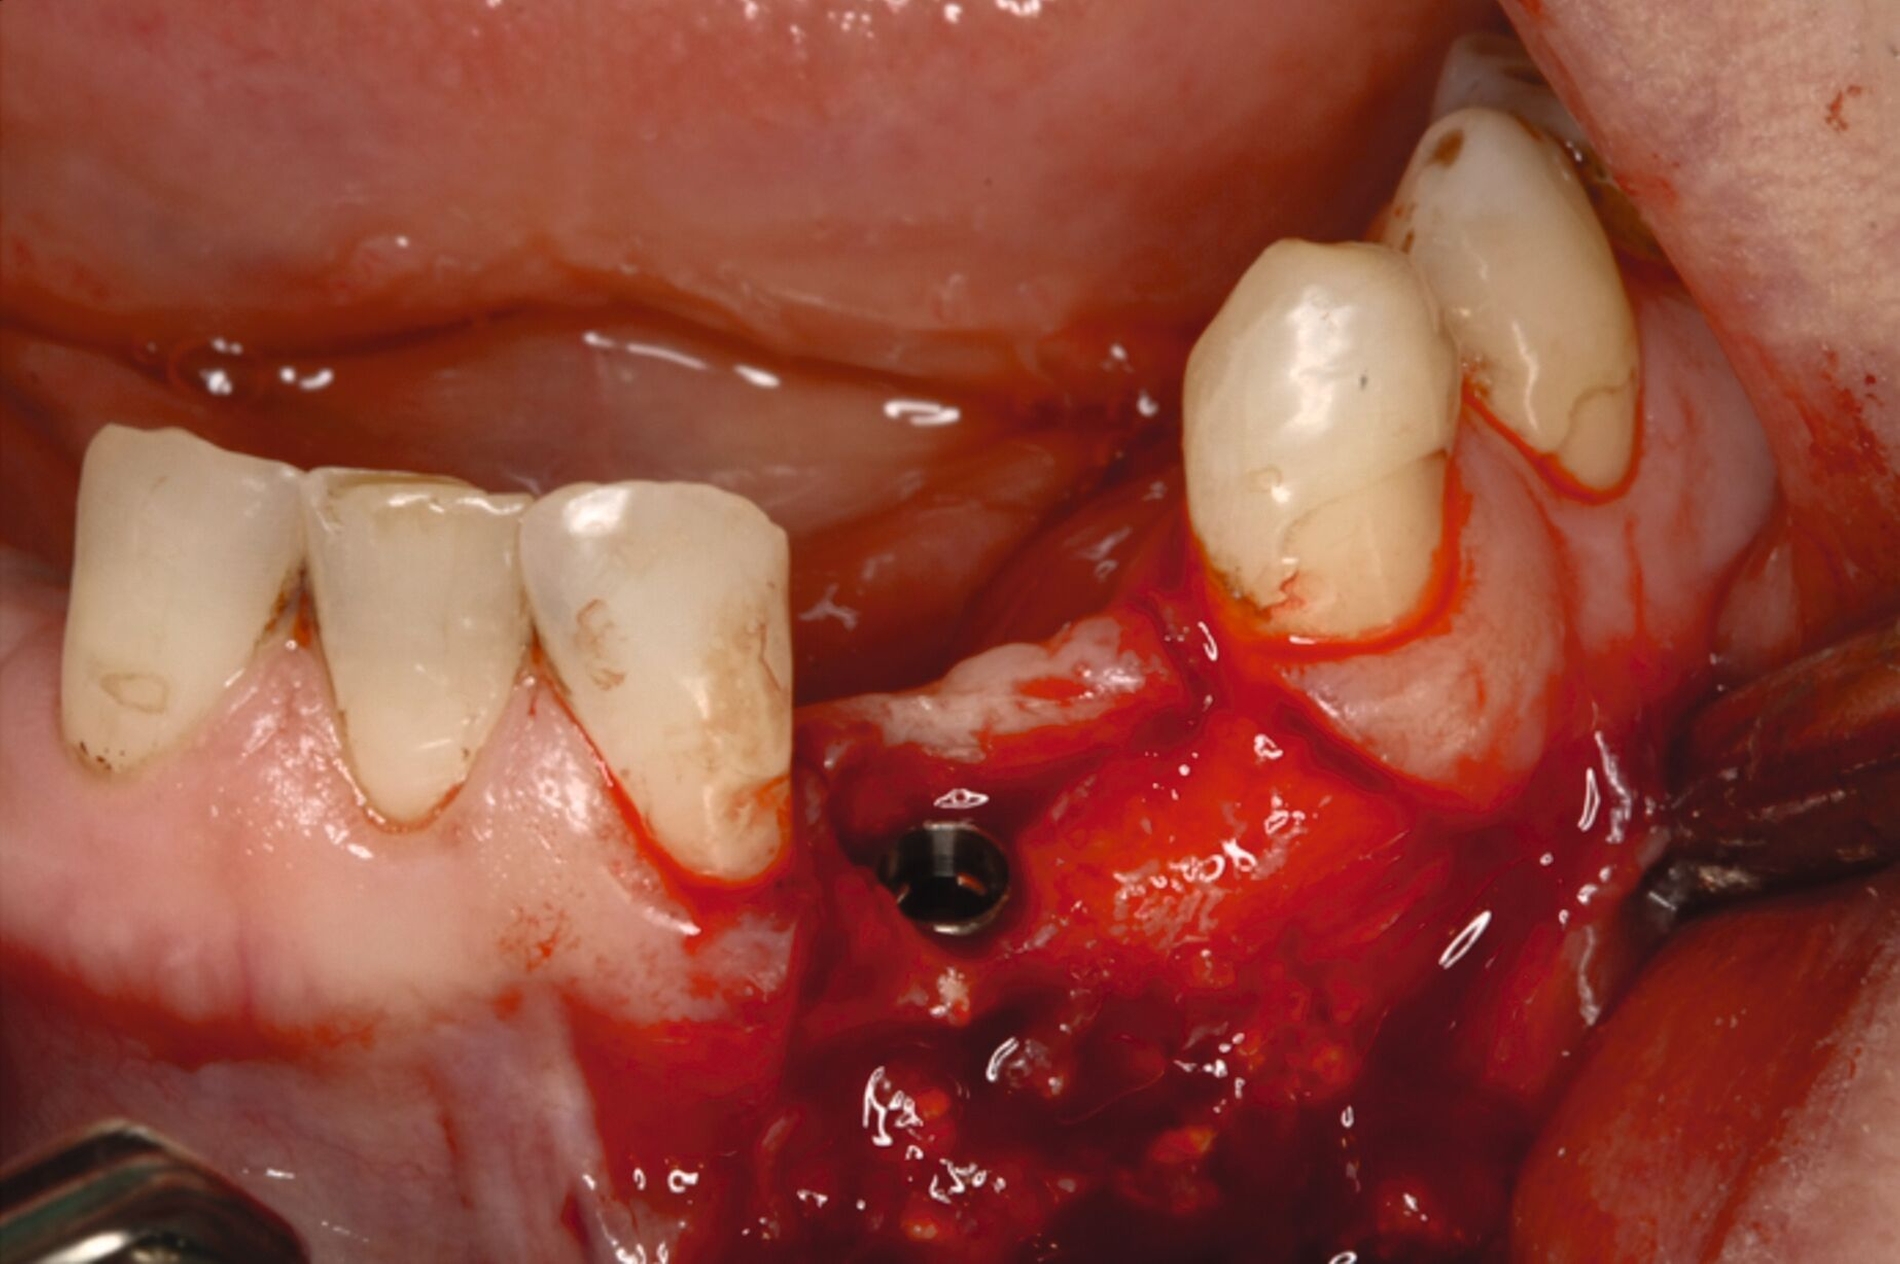

Unter intravenöser Sedierung wurden Implantate im Ober- und Unterkiefer inseriert, kombiniert mit Sinusbodenelevation und vestibulären Augmentationen. Aufgrund unzureichender Knochenverhältnisse erfolgte an Regio 33 eine zweizeitige augmentative Maßnahme mit Schirmschrauben und Membran (Abbildung 6), gefolgt von der sekundären Implantation nach vier Monaten (Abbildung 7).